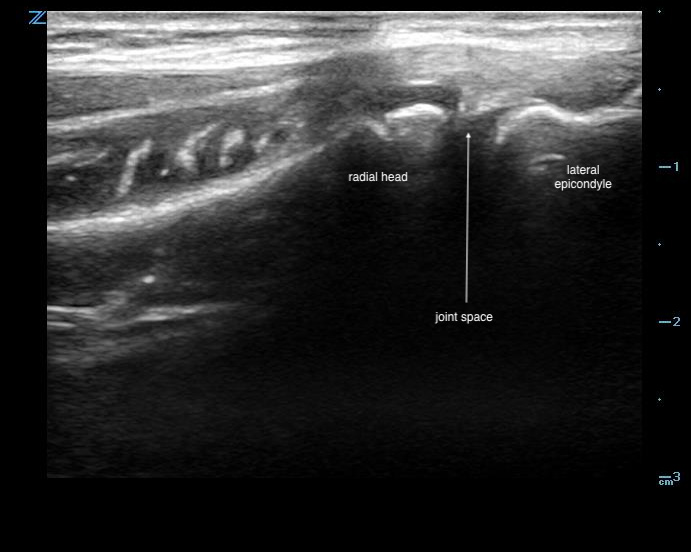

- On the lateral aspect of the elbow, key structures are the capitellum at the lateral epicondyle and its articulation with the radial head distally.

- The common extensor tendon can appear superficially.

- An effusion appears hypo/anechoic within this joint space.7

- Scan proximally to the lateral epicondyle to visualize the space between the radial head and lateral epicondyle.7 (Fig. 11)

- Figure 11. Ultrasound demonstrating normal radiohumeral joint space

- An effusion is an anechoic collection within this space. (Video 3, 4)